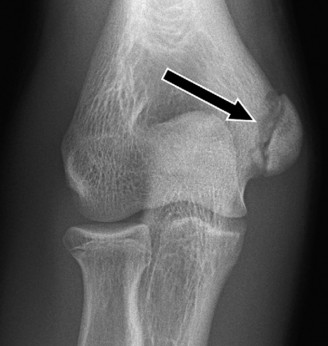

Standard radiographic evaluation of the thrower's elbow must include true anteroposterior (AP), lateral, oblique, and axial (cubital tunnel) views. In this patient, the AP view may appear relatively unremarkable, though subtle hypertrophy of the medial epicondyle or radiocapitellar sclerosis may be noted. The true lateral radiograph is highly informative, often demonstrating the presence of a posterior olecranon osteophyte.

However, the most critical view for diagnosing VEO is the internal rotation oblique view, or a specialized axial view of the olecranon fossa. In our patient's radiographs, we observe a distinct, hypertrophic osteophyte on the posteromedial aspect of the olecranon process. There are also faint radiopacities within the posterior compartment, highly suggestive of intra-articular loose bodies resulting from the fragmentation of these osteophytes.